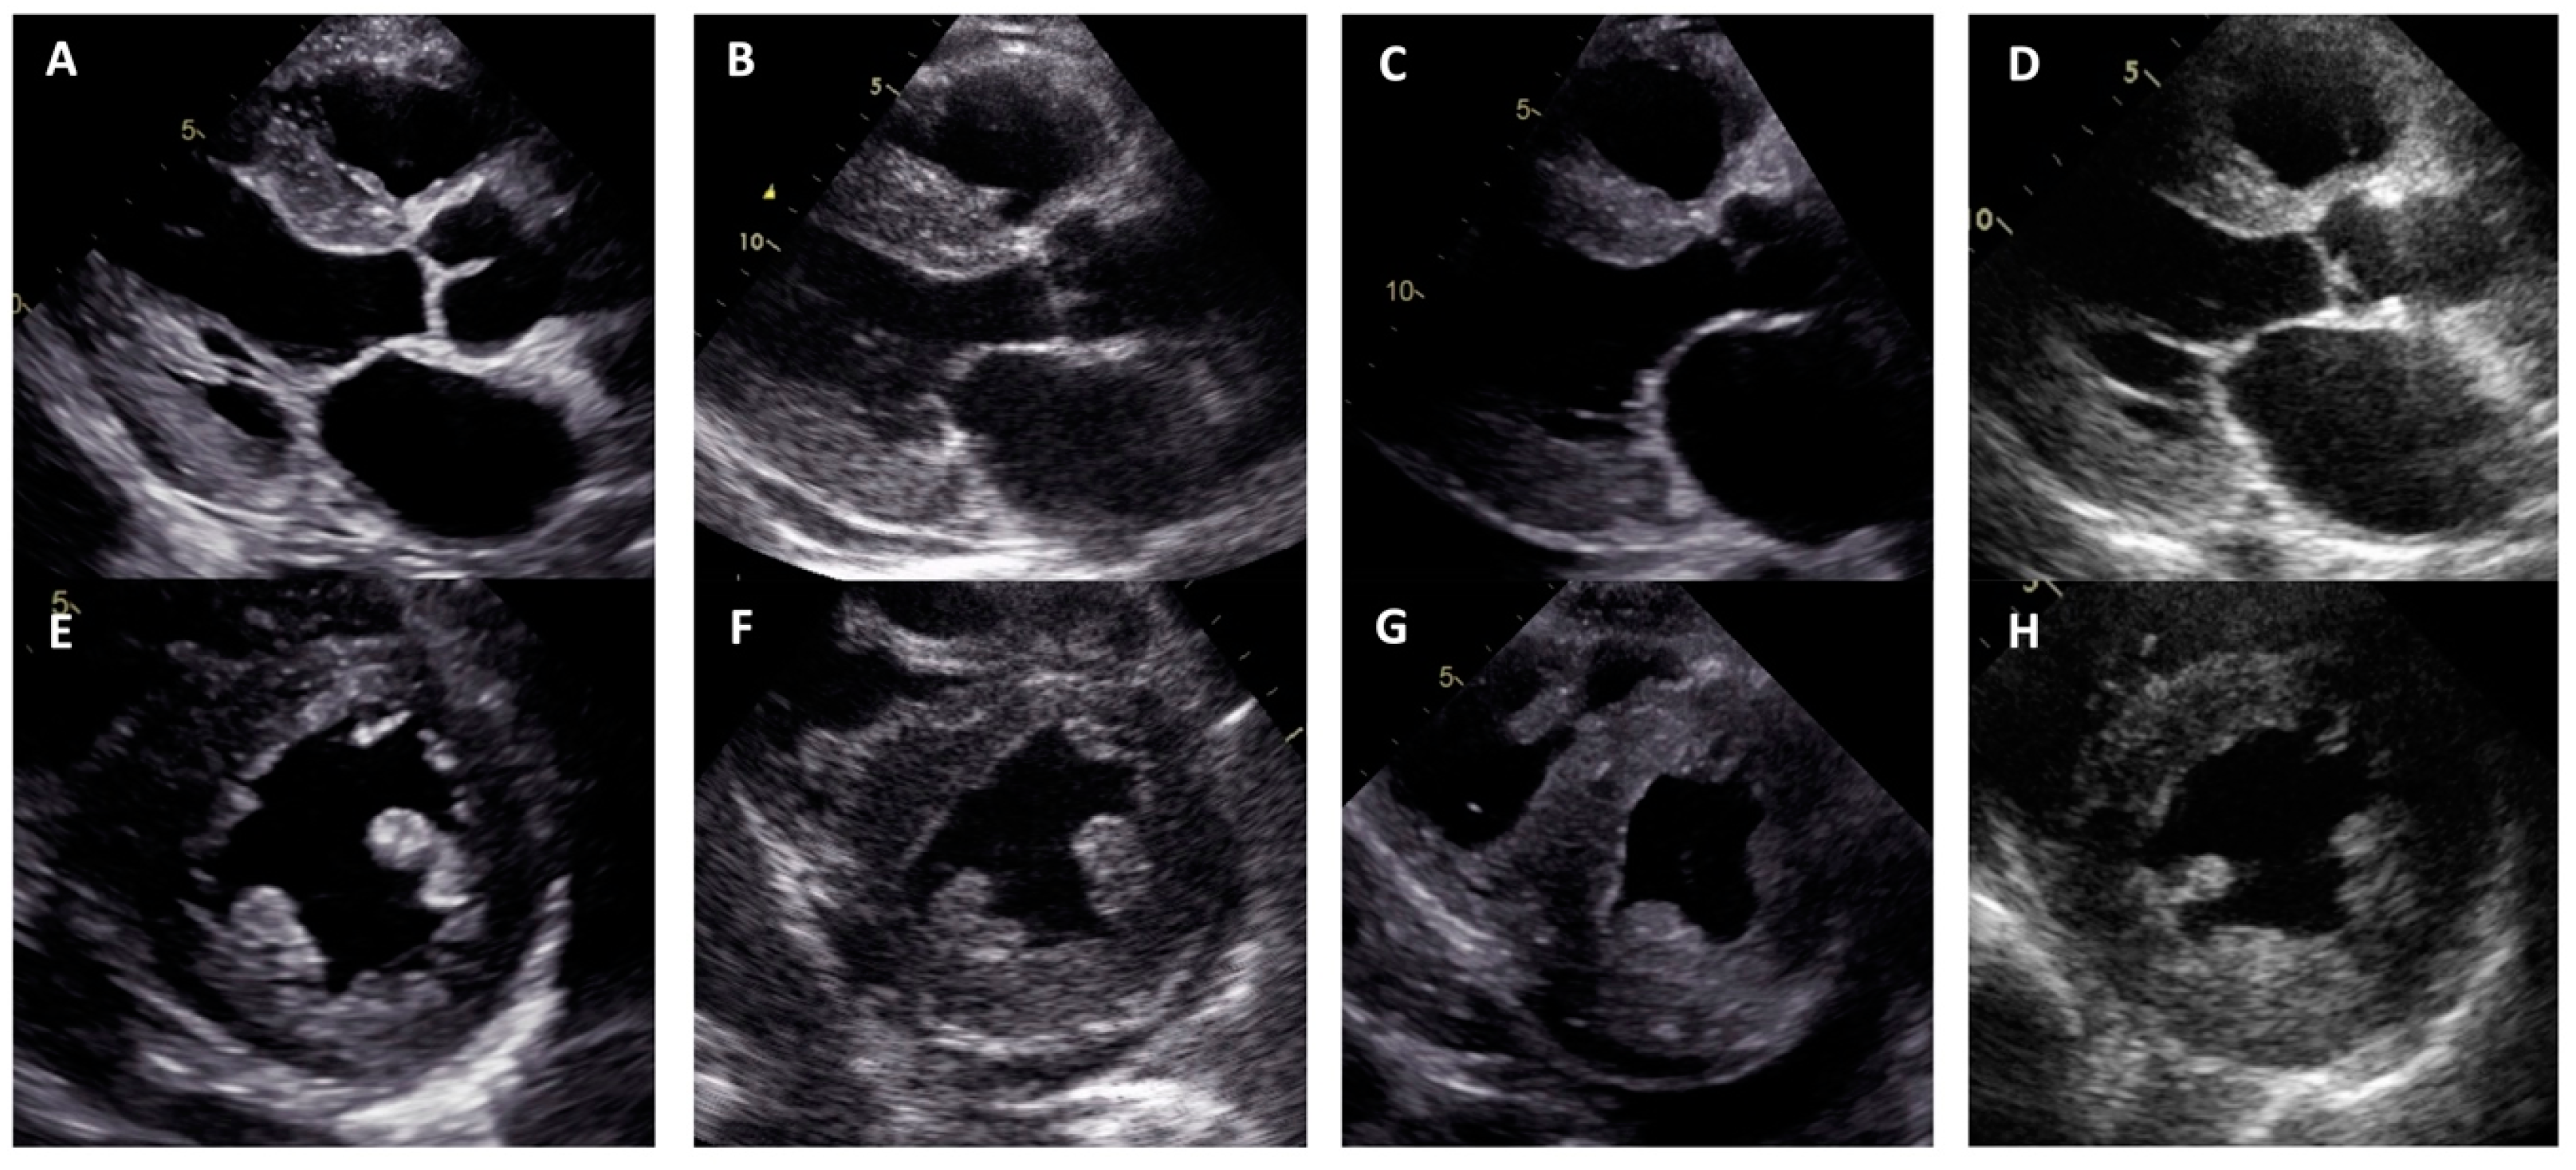

| Proband No. | 1 | 2 | 3 | 4 |

|---|---|---|---|---|

| Zygosity of NM_000371.3:c.302C>T, NP_000362.1:p.(Ala101Val) variant in TTR | Homozygous | Heterozygous | Heterozygous | Heterozygous |

| Sex | Male | Male | Female | Female |

| Age of onset of symptoms (years) | 44 | 74 | 50 | 72 |

| Age at diagnosis (years) | 49 | 77 | 57 | 74 |

| NYHA class of heart failure | III | III | III | III |

| Positive family history | Mother at an older age and aunt on mother‘s side had heart disease | Brother had heart disease | Mother had heart disease, grandmother on mother‘s side had sudden death | Mother and brother died of stroke at an older age |

| Low QRS voltage | - | + | + | + |

| Pseudoinfarct pattern on ECG | - | - | - | - |

| Conduction disturbances | RBBB, LAFB | LBBB | - | LBBB |

| Atrial fibrillation | - | + | + | - |

| LV hypertrophy | Concentric | Concentric | Concentric | Concentric |

| Maximal wall thickness (mm) | 13 | 21 | 14 | 19 |

| LVEF (%) | 67 | 10 | 55 | 40 |

| Restrictive LV filling pattern | - | + | + | + |

| Increased RV wall thickness | + | + | - | + |

| Pericardial effusion | - | + | - | - |

| Cardiac MRI LV hypertrophy | Asymmetric (predominantly in transventricular septum) | Symmetric | Symmetric | Symmetric |

| Cardiac MRI maximal wall thickness (mm) | 16 | 19 | 14 | 20 |

| Cardiac MRI LVEF (%) | 77 | 45 | 50 | 44 |

| Cardiac MRI LGE | Midmyocardial LGE in LV septum and inferior wall | Diffuse subendocardial LGE in LV and RV | Diffuse midmyocardial LGE in LV and RV | Diffuse subendocardial LGE in LV and RV |

| 99mTc-PYP bone scintigraphy | Grade 0 | - | - | Grade 3 |

| Histological confirmation | Amyloid deposits, likely non-specific reaction to transthyretin on immunohistochemistry in bone marrow trepanobiopsy and endomyocardial biopsy | TTR amyloid deposition in adipose tissue biopsy | TTR amyloid deposition in endomyocardial biopsy | - |

| NT-proBNP (pg/mL) * | 474 | 11401 | 3368 | 2471 |

| Troponin I (ng/L) * | 111 | 95 | 65 | 45 |

| Polyneuropathy | + | - | - | + |

| Chronic kidney disease | - | + | + | - |

| Gastrointestinal manifestation | + | + | - | - |

| Carpal tunnel syndrome | - | - | + | + |

| Biceps tendon rupture | - | NA | - | - |

| Follow-up after diagnosis (years) | 3 | 2 | 3 | 1 |

| Outcome | Death at age 52 due to pneumonia complications | Death at age 79 due to colon adenocarcinoma | Death at age 60 due to heart failure decompensation | Death at age 75 due to heart failure decompensation |

| Family segregation analysis | NA | Variant identified in phenotypically negative 47-year-old daughter | Variant identified in phenotypically negative 33-year-old daughter | NA |